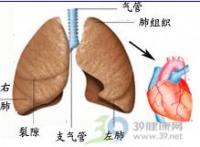

肺原性心脏病(cor pulmonale,简称肺心病)主要是由于支气管-肺组织或肺动脉血管病变所致肺动脉高压引起的心脏病。根据起病缓急和病程长短,可分为急性和慢性两类。临床上以后者多见。

慢性肺原性心脏病(chronic pulmonary heart disease)是由于肺、胸廓或肺动脉血管慢性病变所致的肺循环阻力增加、肺动脉高压、进而使右心肥厚、扩大,甚至发生右心衰竭的心脏病。

慢性肺原性心脏病(慢性肺心病)是指由于肺组织、胸廓或肺动脉的慢性病变逐渐引起肺循环阻力增加、肺动脉高压,进而引起右心室肥厚、扩大,最后发生右心功能衰竭的心脏病.由慢性基础疾病发展为肺心病一般需要10~20年的过程.我国慢性肺心病的患病率北方高于南方,寒冷地区高于温暖地区,高原地区高于平原地区,农村高于城市,吸烟者高于非吸烟者,且随增龄而升高,<60岁者患病率为1.55%、60~69岁为14.98%、≥70岁为20.80%.老年患者占同期慢性肺心病的80.08%,占同期心脏病患者的19.44%,仅次于冠心病,是主要危害我国老年人健康的第二位心脏病.